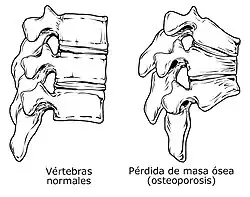

La osteoporosis es el término general para definir la porosidad del esqueleto causada por una reducción de la densidad ósea. En esta enfermedad existe una disminución de la resistencia del hueso, debido a una alteración en la remodelación ósea, por ello hay un descenso de la masa ósea, además de presentarse conductos amplios de reabsorción; en tanto que la concentración de calcio en la matriz es normal.

La osteoporosis secundaria es la más frecuente y suele aparecer asociada con la tercera edad y la menopausia. En homeostasis la unión del estrógeno con los osteoblastos a través de receptores específicos, estimula a los osteoblastos para producir y secretar matriz ósea. Con el decremento de la secreción de estrógeno por la menopausia, la actividad osteoclástica (reabsorción) se vuelve mayor que la osteoblástica (formación de tejido óseo nuevo), teniendo como consecuencia la reducción de la masa ósea, volviendo frágil al hueso, por incapacidad para el soporte de las fuerzas de tensión.

No obstante, hay un número considerable de causas secundarias de osteoporosis a cualquier edad que no suelen ser reconocidas ni valoradas, pero que se pueden identificar si se somete al paciente a una evaluación apropiada. Entre ellas destacan la deficiencia de calcio y vitamina D, la actividad física reducida, la enfermedad celíaca y la sensibilidad al gluten no celíaca no diagnosticadas ni tratadas, la diabetes mellitus, la insuficiencia renal, la acidosis tubular renal y los tratamientos con corticoides de larga duración.[23][24][25][26] En las personas con enfermedad celíaca o sensibilidad al gluten no celíaca con enfermedad activa, causa la osteoporosis y no se limitan a posibles carencias nutricionales, sino también a procesos inflamatorios o autoinmunes, en los que el consumo de gluten provoca el desarrollo de autoanticuerpos que atacan a los huesos.[25][27]